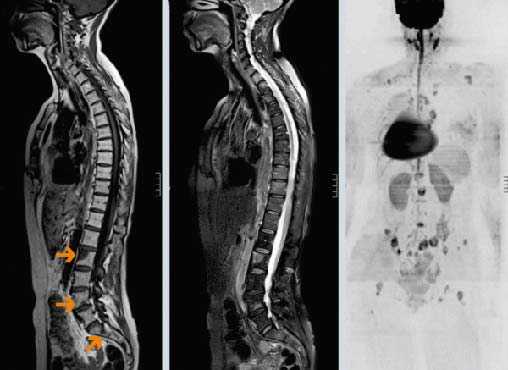

Чем дольше живет больной со злокачественной опухолью, тем выше вероятность метастазирования рака. Нередко метастазы обнаруживаются в позвоночнике. Они могут вызывать боли и часто бывают гиперваскуляризированы (имеют большое количество сосудов), что делает хирургические вмешательства довольно проблематичными. Предоперационная эмболизация позволяет эффективно деваскуляризировать (обескровить) опухоль, за счет чего уменьшается кровотечение и улучшается обзор во время операции.

Перед процедурой эмболизации проводят ангиографическое исследование. В сосуды вводят раствор рентгенконтрастного вещества, благодаря чему питающие опухоль артерии прокрашиваются и становятся хорошо видны на рентгенограммах. Врач получает информацию о кровоснабжении новообразования и особенностях сосудистой сети. Например, становится понятно, из какой позвоночной артерии получает кровь патологическое образование в шейном отделе позвоночника: из правой или из левой.

Почти две трети метастазов позвоночника гиперваскуляризированы. О степени васкуляризации (плотности сосудистой сети) опухоли можно судить по ее гистологическому строению. Неоваскуляризация (патологическое разрастание сосудов) особенно активна в опухолях, которые происходят из ткани почек, эндокринных органов, зародышевых клеток. Быстрорастущая опухоль, которая приводит к патологическому перелому, вероятно, тоже будет гиперваскуляризирована.

К сожалению, когда рак метастазирует, он может трансформироваться в более агрессивную быстрорастущую форму. Поэтому врачи не могут опираться только на данные гистологических исследований. Иногда метастазы прорастают в ткани, в которых очень сложно достичь остановки кровотечения при помощи электрокоагуляции или перевязки сосуда.

- магнитно-резонансную томографию;